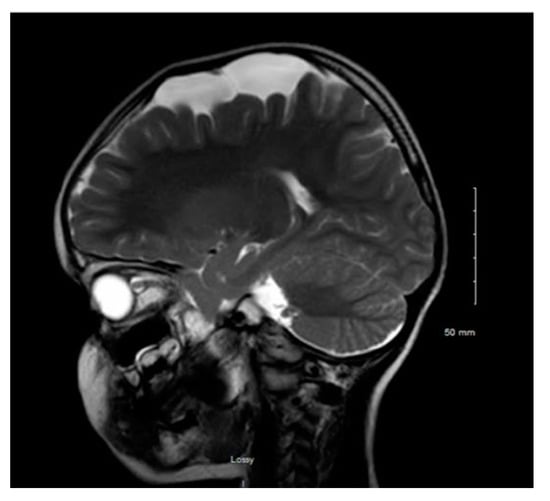

Figure 1 and Figure 2 reveal a change in signal of arachnoid cyst suggestive of interval hemorrhage with a thin subdural hematoma along its inferior aspect. Minimal edema in the subjacent Rolandic cortex was present. Given the patient’s stroke-like presentation, an MRA of head and neck was administered, which was found to be normal. The findings, with a comparison of the previous MRI of the patient at age 4 (Figure 3 and Figure 4), are consistent with a ruptured arachnoid cyst. No acute neurosurgical intervention was performed due to the absence of raised intracranial pressure and reduction of neurological symptoms. A routine EEG performed in the emergency department exhibited interictal epileptiform discharges over the left and right central–temporal region during drowsy and sleep states, suggestive of increased risk for partial seizures from these regions.

Figure 3. MRI T2WI, sagittal section in 2012 (4 years of age).